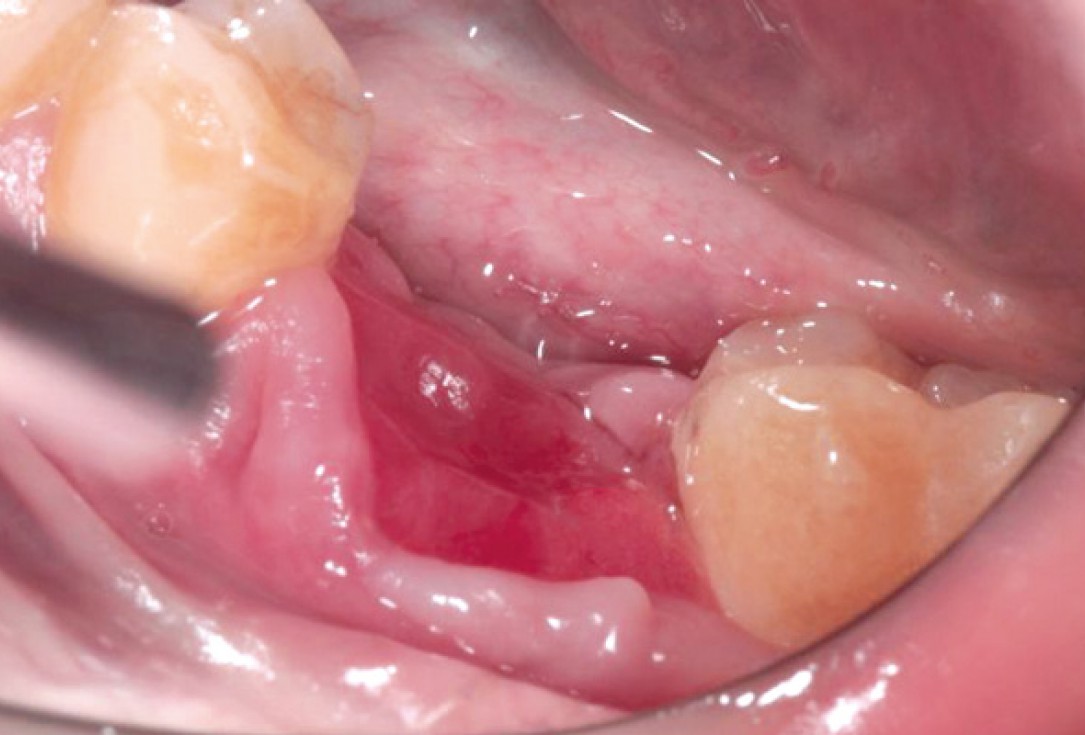

Situation after tooth extraction.